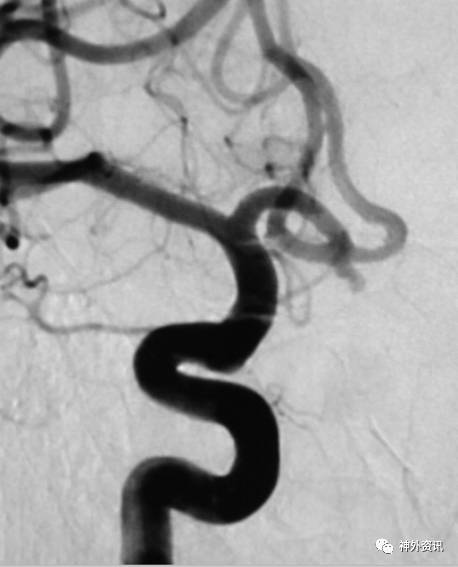

眼动脉动脉瘤,支架完全释放后,微导管成袢逆行到位

病例二

眼动脉动脉瘤,支架释放前,微导管成袢逆行到位

病例三

A1起始段动脉瘤,微导管成袢逆行到位

病例四

海绵窦区硬脑膜动静脉瘘,海绵窦下外侧干超选栓塞